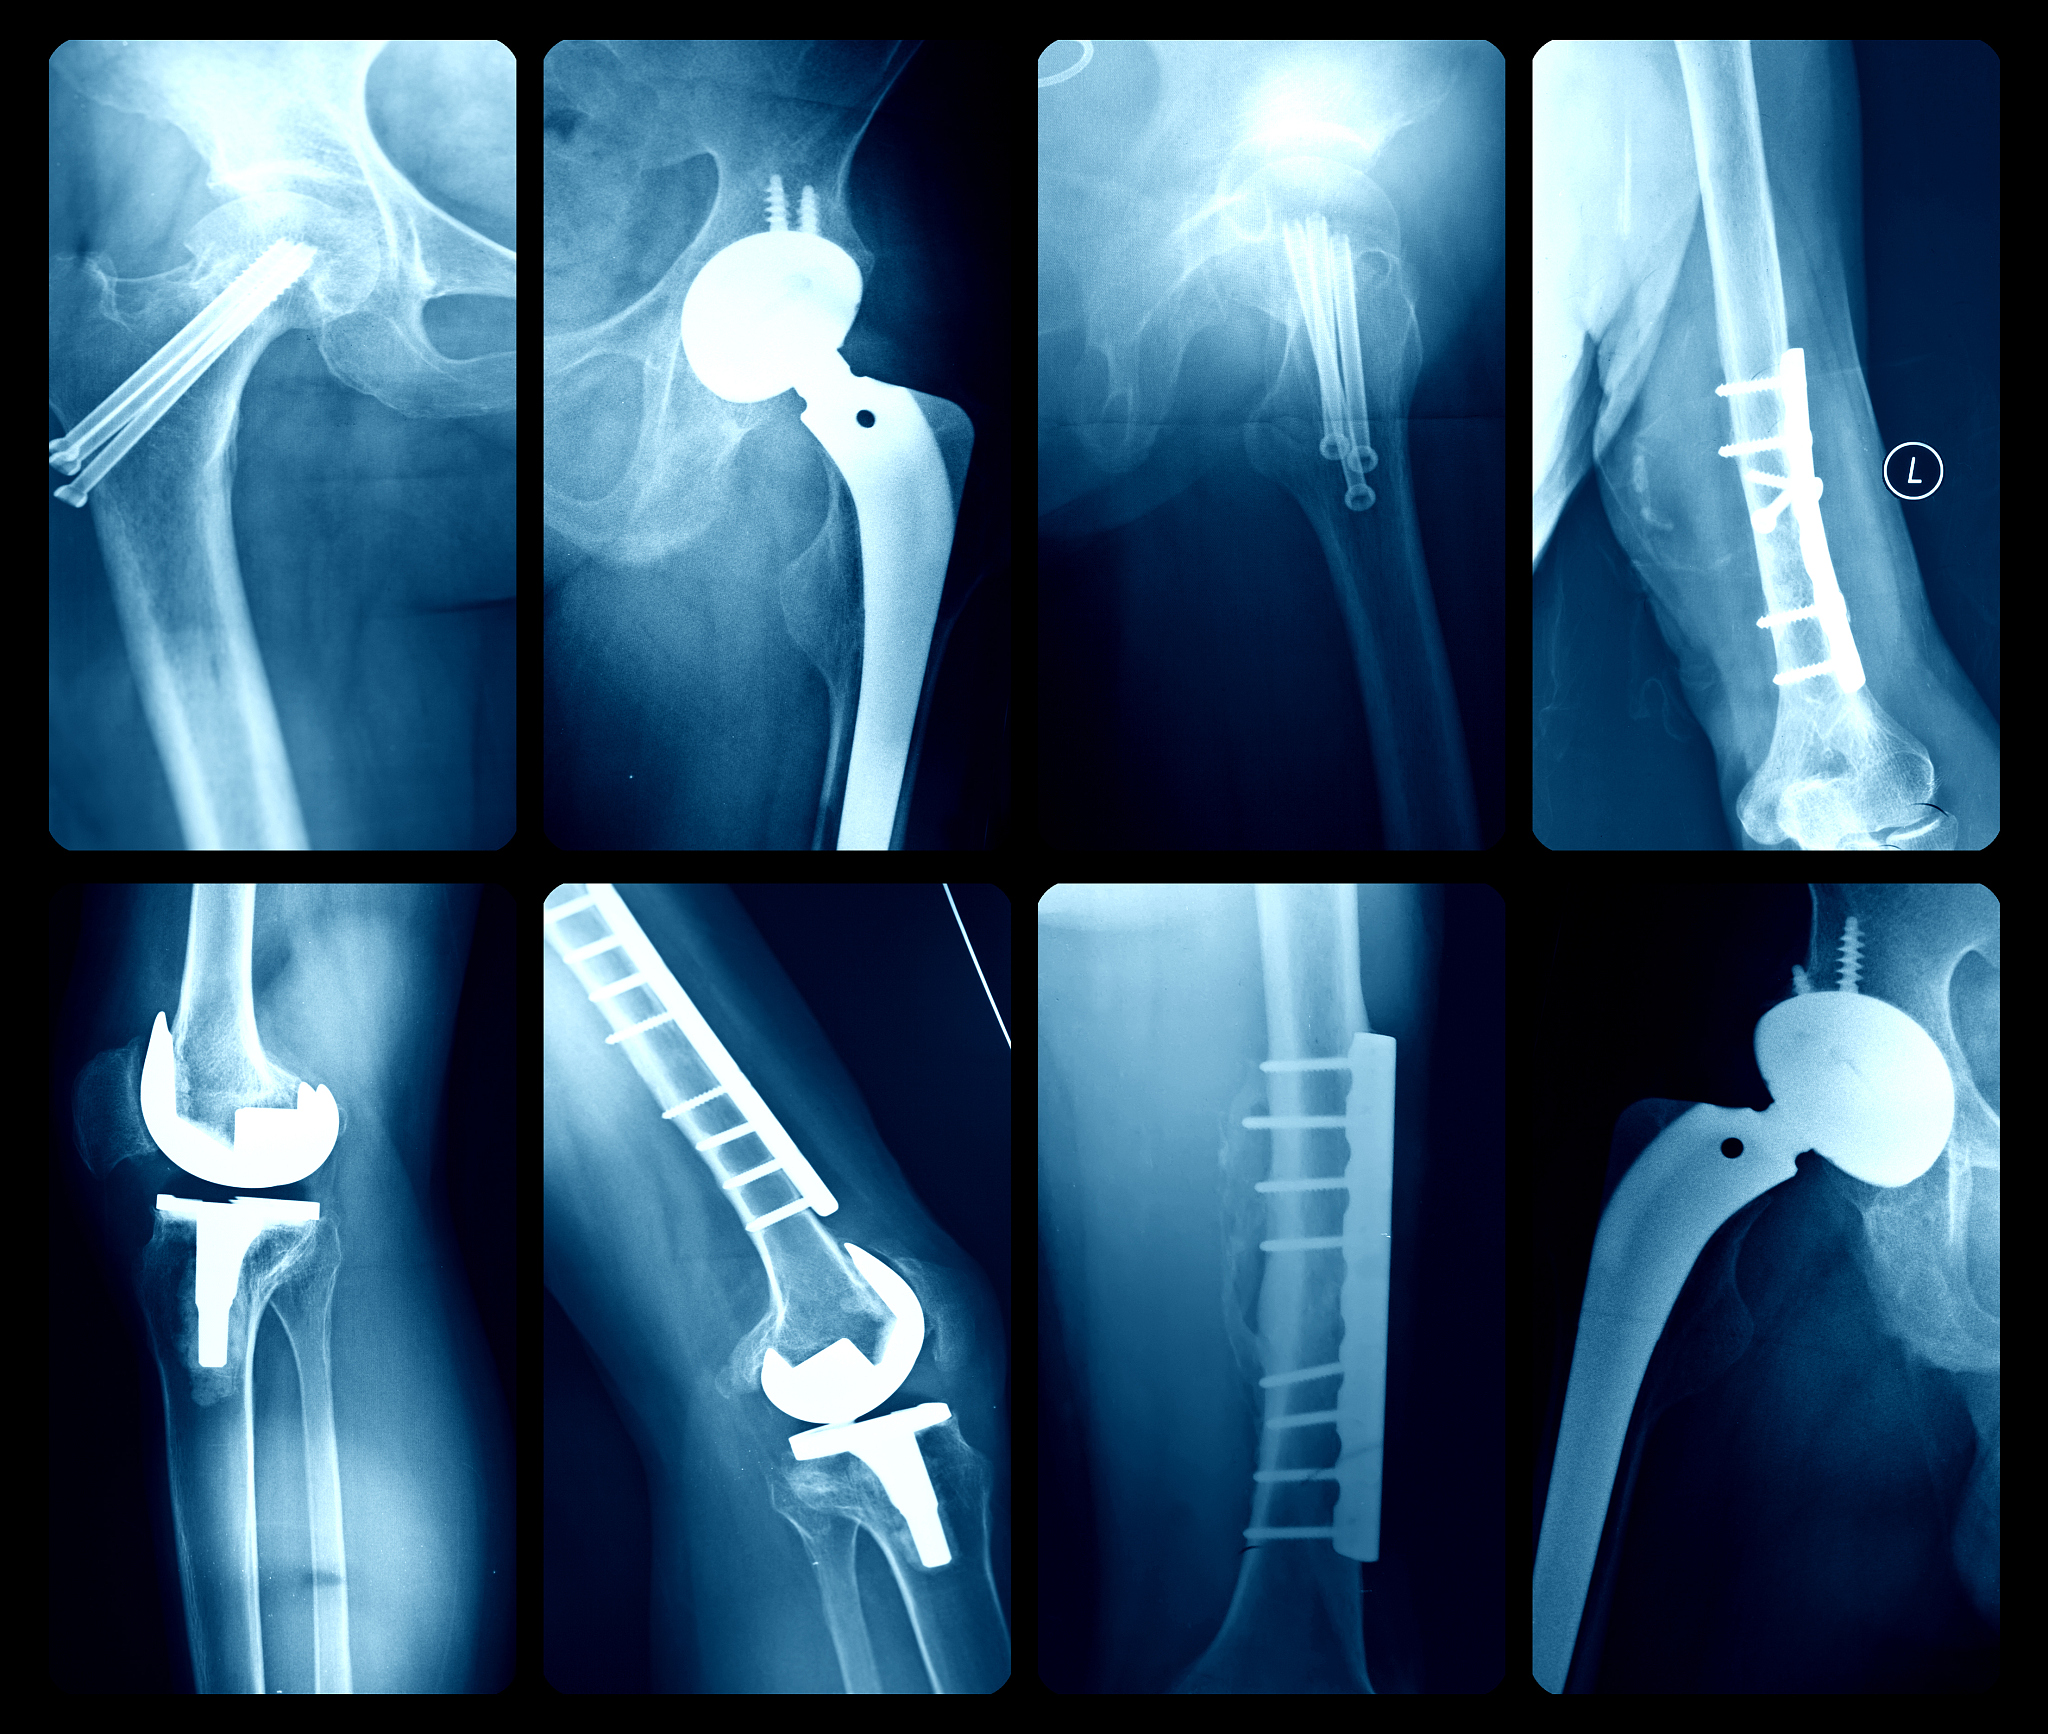

股骨近端防旋髓内钉内固定治疗高龄患者髋部骨折的优势包括:

1. 保留了患者的骨骼完整性:通过内固定手术,股骨近端防旋髓内钉可以将骨折部位重新定位并固定,保留了患者的骨骼完整性,有利于骨折的愈合。

2. 手术创伤小:相比传统的开放手术,股骨近端防旋髓内钉手术创伤较小,只需要进行几个小切口,减少了手术对患者的创伤。

3. 术后恢复快:内固定手术后,患者可以早期进行康复训练,恢复关节功能,减少了术后的康复时间。

4. 减少了感染和并发症的风险:内固定手术创伤小,术后感染和其他并发症的风险相对较低。

5. 对高龄患者的心肺功能要求较低:相比开放手术,内固定手术对患者的心肺功能要求较低,适合高龄患者进行手术治疗。

需要注意的是,股骨近端防旋髓内钉内固定手术也存在一些风险和并发症,如感染、内固定松动或断裂等,术前应充分评估患者的适应症和手术风险。

股骨近端防旋髓内钉内固定治疗高龄髋部骨折优势